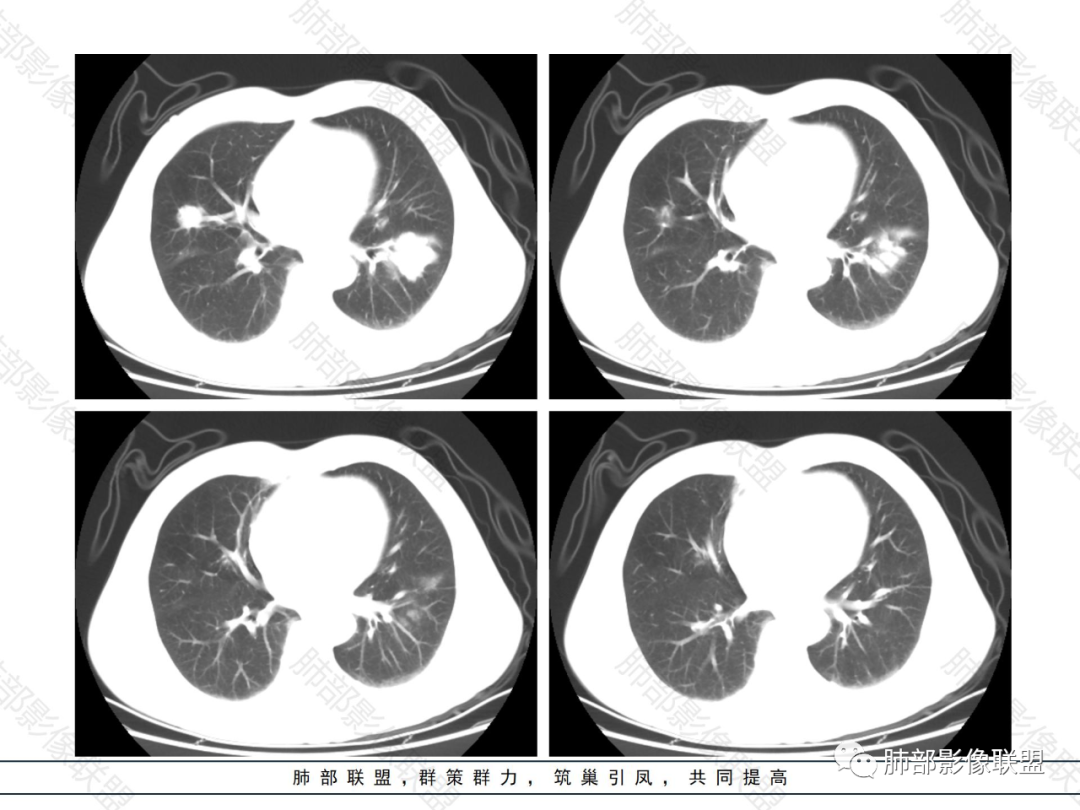

双肺多发大小不等结节,以胸膜下为主,部分边缘平直,彭隆,整体较密实,临床无症状体检发现,考虑淋巴瘤,转移瘤,IMT.

老年男性,发现占位半年,双肺多发结节,病灶边界清晰,浅分叶,部分支气管进入后堵塞,部分病灶内部密实,无增强,考虑真菌感染,淋巴瘤待排除。

双肺多发结节肿块,部分位于胸膜下,部分结节内可见扩张支气管,右肺上叶近肺门处结节呈分叶毛刺,支气管阻塞、扭曲扩张,考虑1淋巴瘤2腺癌转移。

双肺多发结节,密度均匀,部分可见支气管进去后堵塞,有胃部手术史,考虑淋巴瘤?鉴别腺癌转移,其他?

脾大表现,两肺叶多发结节,部分呈肿块(浅分叶轮廊),实性密度,边缘清楚,有膨隆,近胸膜下分布,支气管僵直略扩张,一元论,首选淋巴瘤。

双肺多发结节肿块,胸膜下支气管树旁为主,部分内可见支气管穿行,支气管扩张。淋巴瘤?肉芽肿性多血管炎?鉴别转移

必有路:老年男性,两肺多发结节,团块,病灶都位于胸膜下,血管相关,有支气管充气征,分叶,无坏死,周围无晕疾病谱:隐球菌病,GPA,OP,malt,转移,IgG4相关,栓塞诊断:鉴于患者体检发现半年,症状逍遥重点考虑 淋巴瘤 可能鉴别:隐球菌病,GPA,IgG4相关,转移

多发团块影,胸膜下为主,边缘清楚、膨隆、平直,部分病灶可见分叶,病灶内支气管穿行,血管穿行,考虑淋巴瘤。

刚看了视频,老年男性,体检发现,30年前有胃部手术史。双肺野多发结节肿块影,沿支气管血管束或胸膜下分布,有的结节内似有小空洞,支气管进入走形自然,肿块边缘膨隆,有分叶,支气管进入后有的截断,大部分支气管穿过,走形自然,纵隔内未见明显肿大淋巴结,总体考虑淋巴瘤,炎性肉芽肿(肉芽肿血管炎或隐球菌肺炎)等。考虑后者可能性大,肉芽肿血管炎或隐球菌肺炎,鉴别淋巴瘤。

病变分布特点,胸膜下,叶间胸膜下为主,呈大小不等结节级团块影,部分病灶内见支气管影,病灶收缩不明显,从分布及慢性发病看,隐球和淋巴瘤都可,补充增强,病灶内见血管穿行,强化不明显,支持淋巴瘤

老年男性,两肺多发结节肿块,胸膜下分布为主,部分支气管进入闭塞,增强扫描有强化,血管穿行无破坏,边缘尚光滑,周围无晕,病灶整体膨隆为主,半年病程,症状逍遥,首先考虑淋巴瘤

棉花糖:双肺多大小不等结节,边缘清楚,无毛刺,浅分叶,胸膜下分布为主,内可见支气管穿行,增强后中等程度强化,病灶内血管走行自然,考虑淋巴瘤,鉴别GPA